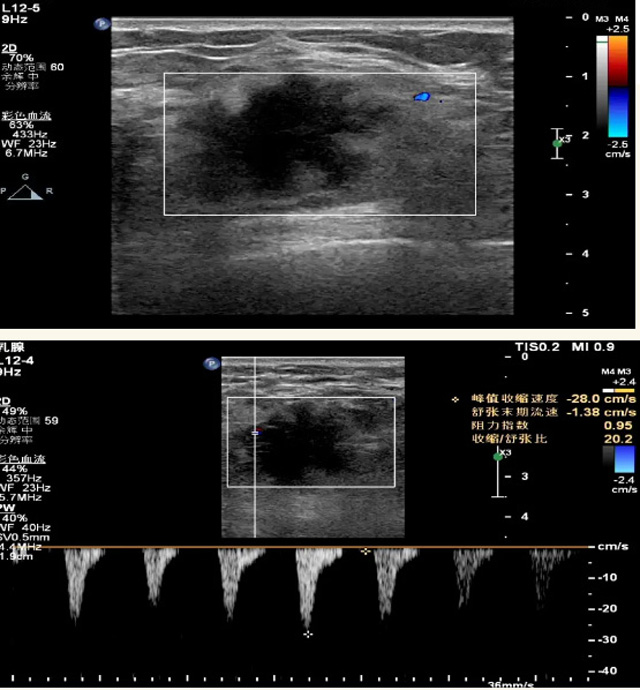

乳腺B超檢查無輻射,對囊性病變敏感,可以實(shí)時(shí)觀察病灶。超聲引導(dǎo)活檢跟手術(shù)前的定位。就是它對于微小的鈣化查出率比鉬靶稍微差點(diǎn)。磁共振MRI檢查也是是沒有輻射的,對備孕跟已經(jīng)懷孕的人士比較友好。不用擔(dān)心這個(gè)輻射影響胎兒問題。對乳腺病灶敏感性較高,致密乳腺病灶、乳腺癌的復(fù)發(fā),準(zhǔn)確鑒別囊性及實(shí)性病變??梢詭椭R床醫(yī)生判斷惡性、良性病變。但是MRI磁共振對微小鈣化不明顯,微鈣化還是鉬靶靠譜點(diǎn)。檢查時(shí)間比較長,有偽影的影響。費(fèi)用相對B超,鉬靶高很多。

乳腺B超